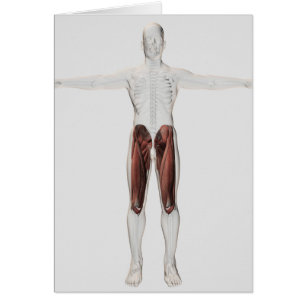

Anatomie Musculaire Masculine Des Jambes Humaines,

Prix de vente 6,48 $CA. Prix Initial 7,20 $CA.

Anatomie Musculaire Masculine Des Jambes Humaines,

Prix de vente 6,48 $CA. Prix Initial 7,20 $CA.